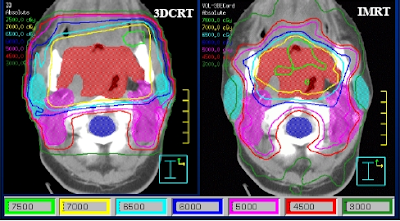

3D-CRT stands for three-dimensional conformal radiation therapy. 3D-CRT is a form of external radiation that matches the radiation beam to the shape of the tumor. In traditional external beam radiation therapy, treatment is provided based on a two-dimensional representation of the body. In 3D-CRT, specialized software is used to convert two-dimensional images into a three-dimensional representation of the body and the tumor. Therefore, the radiation treatment specialists can direct the radiation to the tumor in three-dimensional space. The result of this process is that more radiation is delivered to the tumor and less radiation is delivered to healthy tissue.

Like traditional external beam radiation, the 3D-CRT treatment is painless. Since targeting in 3D-CRT is more precise than in the traditional approach, higher doses of radiation can be used. Thus, the cancer-killing potential of the treatment is higher.

IMRT

IMRT stands for Intensity Modulated Radiation Therapy. Like 3D-CRT, IMRT delivers radiation precisely to areas with tumors while mostly sparing surrounding tissue. Unlike 3D-CRT, IMRT delivers different intensities of radiation to the tumor. For example, a high-intensity beam can be directed at areas of large, solid tumor mass while lower intensity energy can be directed at thinner or smaller collections of cancer cells. Because of this enhanced precision, very high doses of ionizing radiation can be used with IMRT.

IMRT may be more effective than external beam radiation therapy and may cause fewer side effects. When IMRT is compared to 3D-CRT, however, the differences in effectiveness are less impressive. IMRT is able to deliver higher amounts of radiation to the mesothelioma, but it still puts healthy organs at risk.